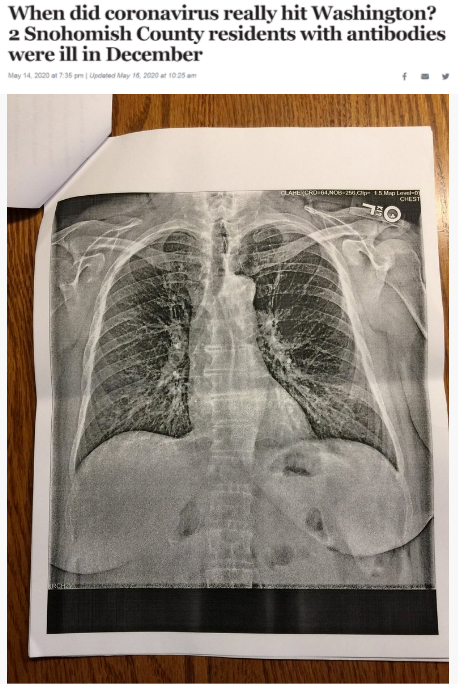

據《西雅圖時報》去年5月14日報道,華盛頓州斯諾霍米什縣的兩位居民在2019年12月出現(xiàn)類似新冠肺炎的癥狀,之后對他們的新冠病毒抗體檢測呈陽性反應。這一結果表明,新冠病毒可能比想象中更早在當?shù)爻霈F(xiàn)。

△《西雅圖時報》報道截圖(題圖中的X光片顯示其中一位斯諾霍米什縣居民的肺部“過度充氣”并出現(xiàn)“線性混濁”。醫(yī)生認為,這可能是疊加上呼吸道肺部感染的表現(xiàn)。)